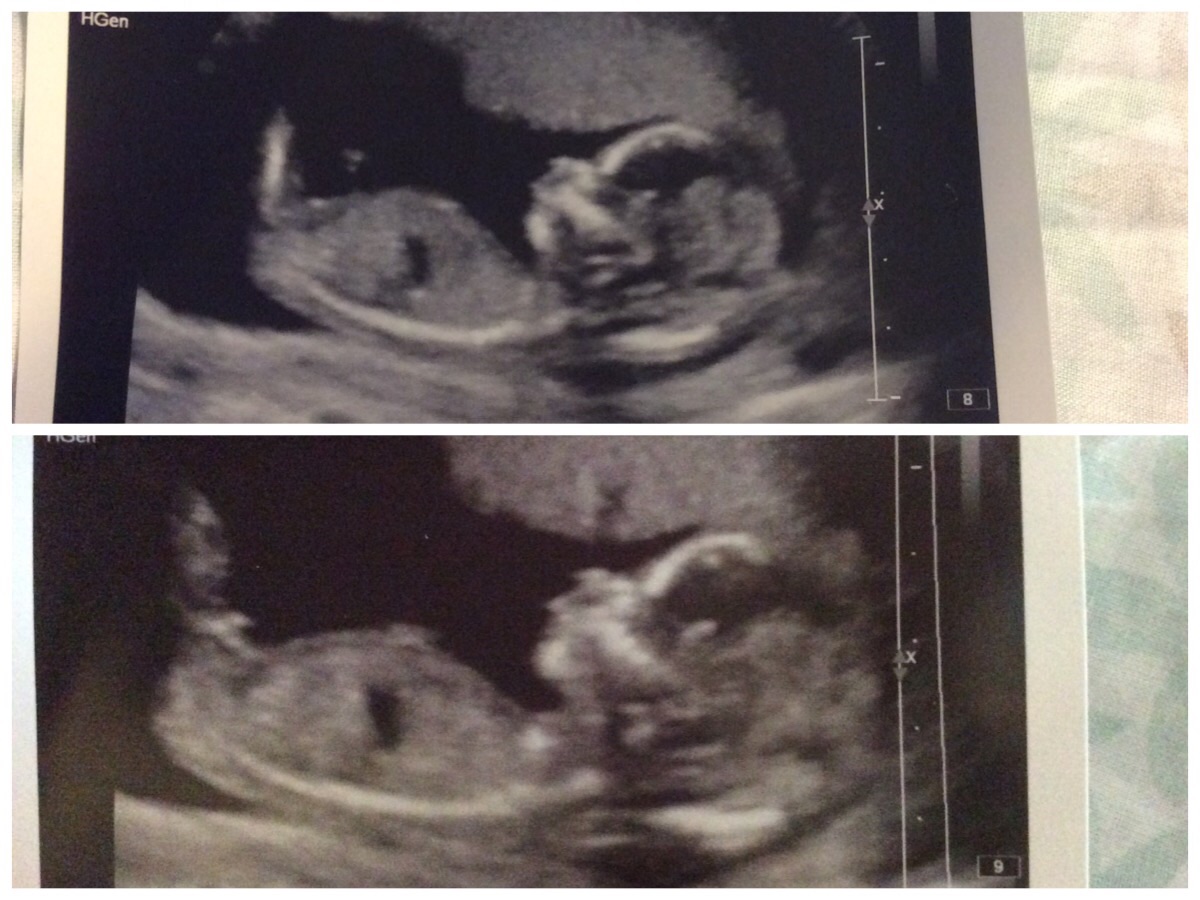

Had my first dating scan yesterday and baby measuring few days ahead, but sonographer did not want to predict gender. Had mostly boy responses so far but looked quite girly on scan xD Many thanks for any guesses - just curiosity and for fun! Attachment 22312